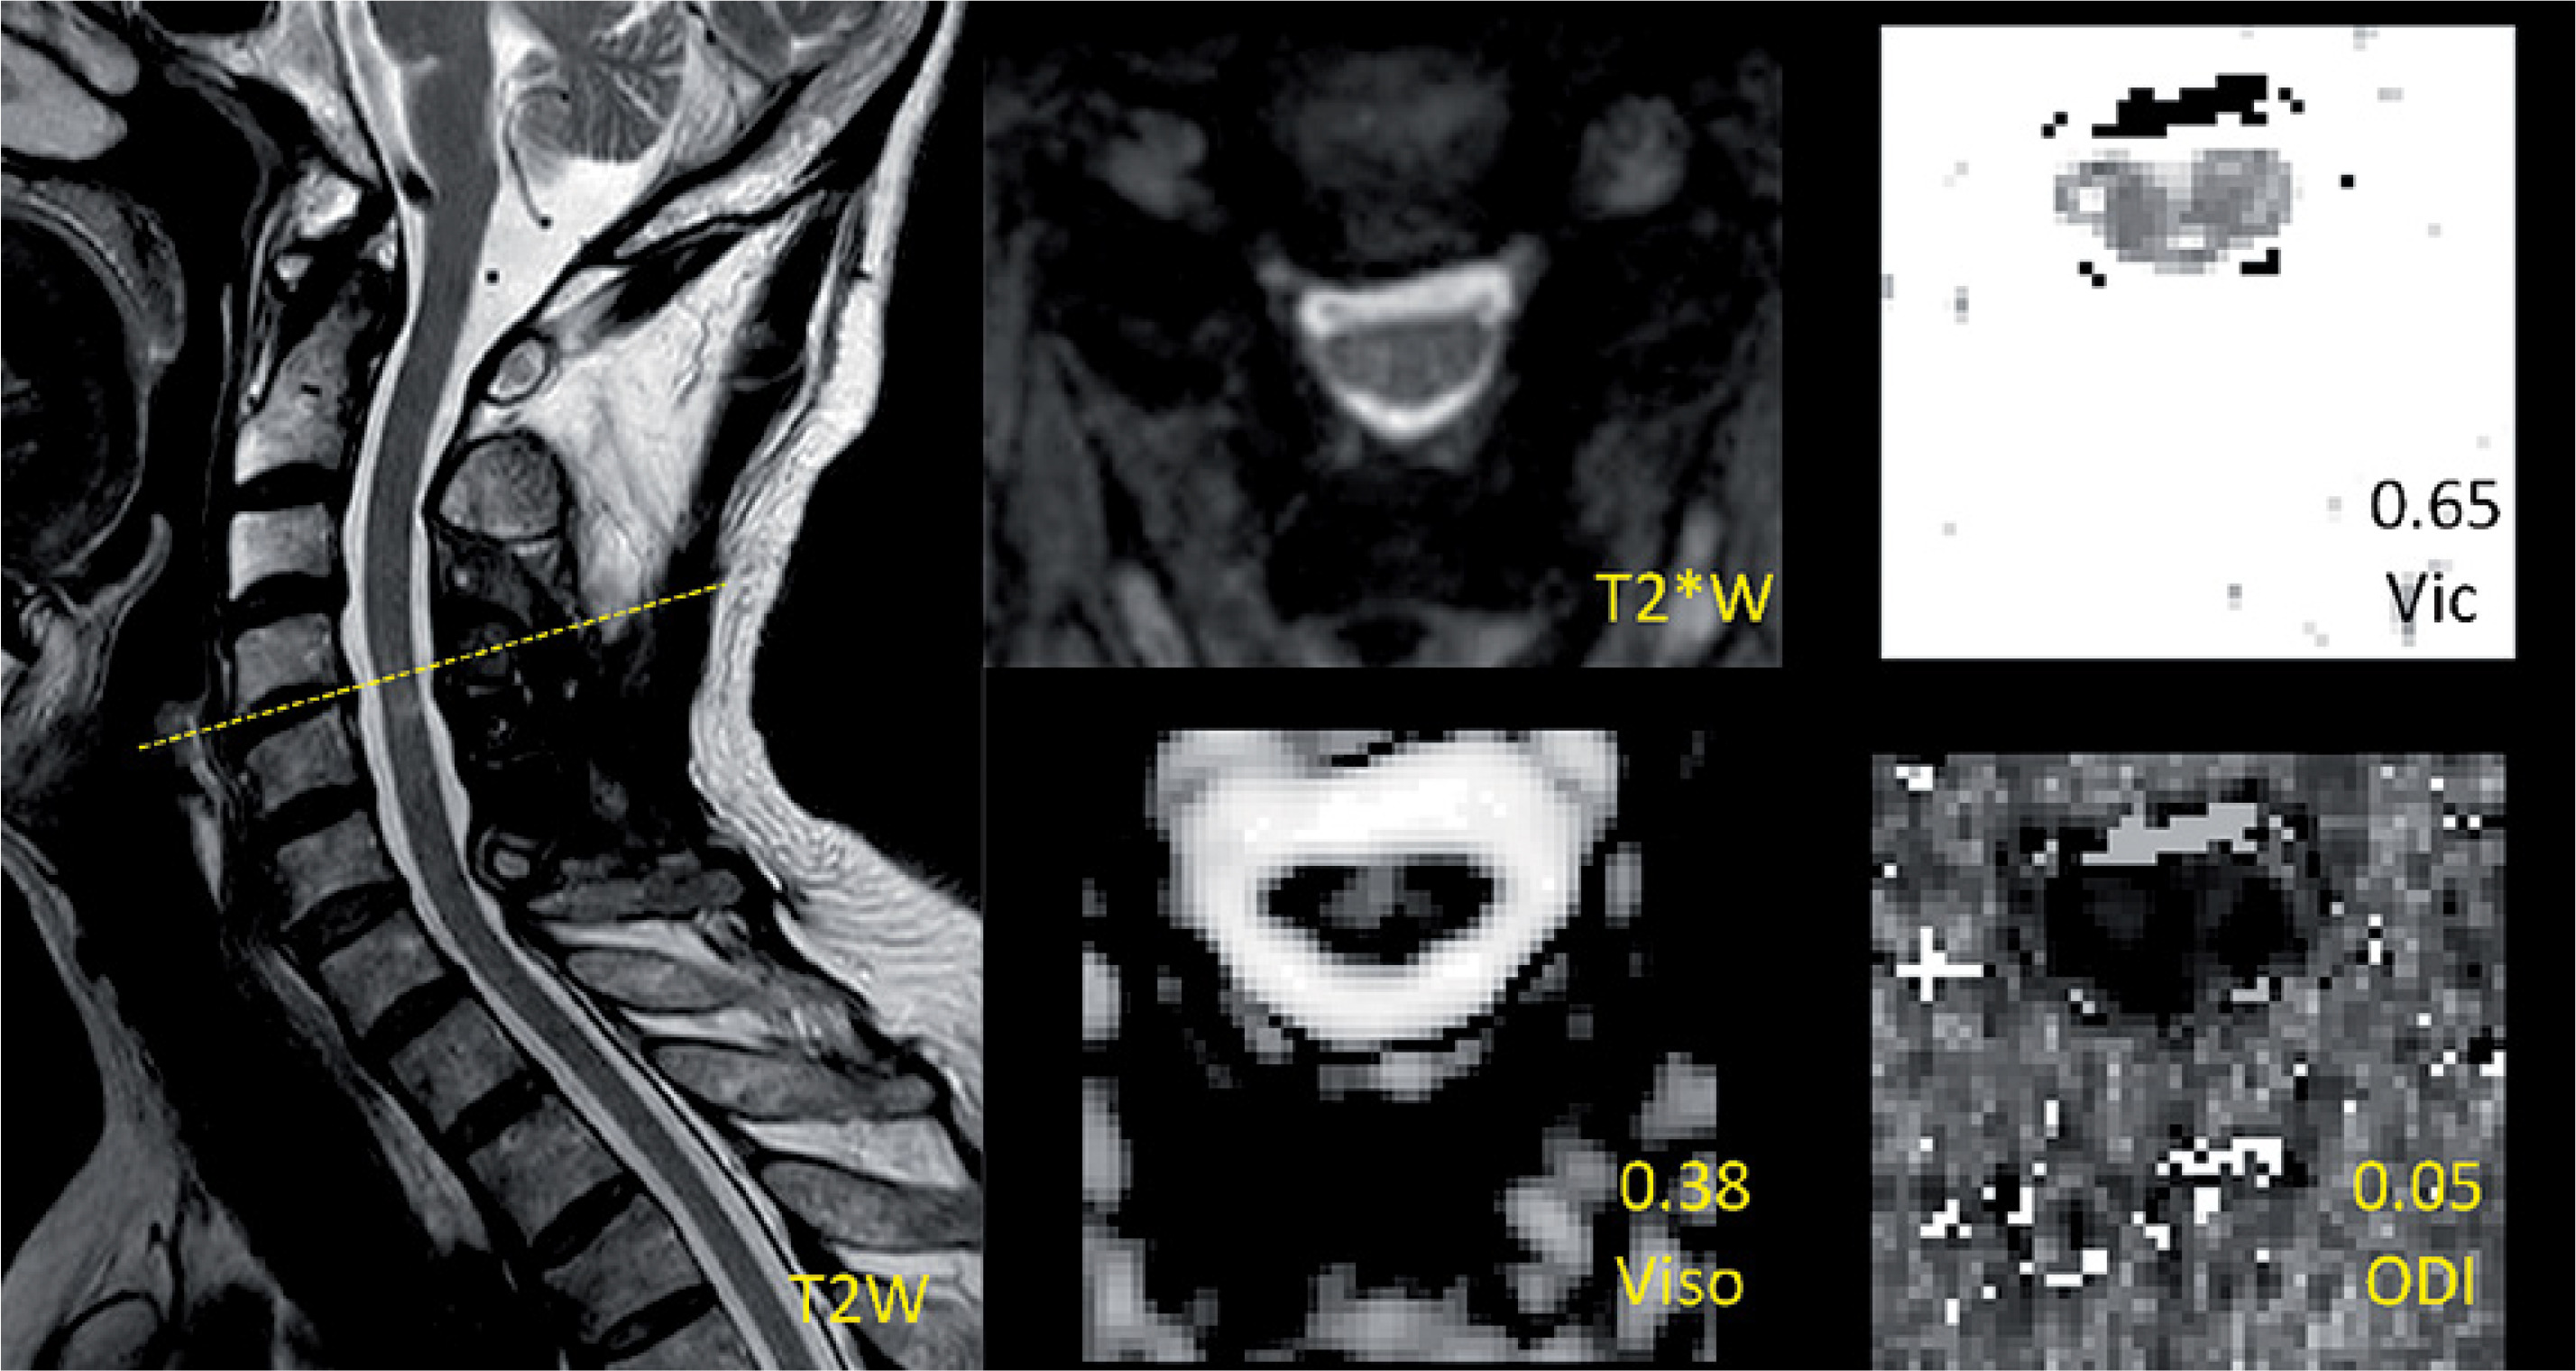

Figure 1

Demonstration of the measurement of a reduced-area (RA) level and images of T2*WI and NODDI metrics and region of interest (ROI) drawing at the level with RA and T2 high signal intensity (T2-HSI) in a postoperative CSM patient. The measurement is the ratio of the most compressed cross section area (Slice 1) to the proximal normal area in the cranial direction (Slice 2). The ratio of this case is about 0.48 and thus this case was placed in the RA group. The values of NODDI metrics in the ROI are presented above the metrics description